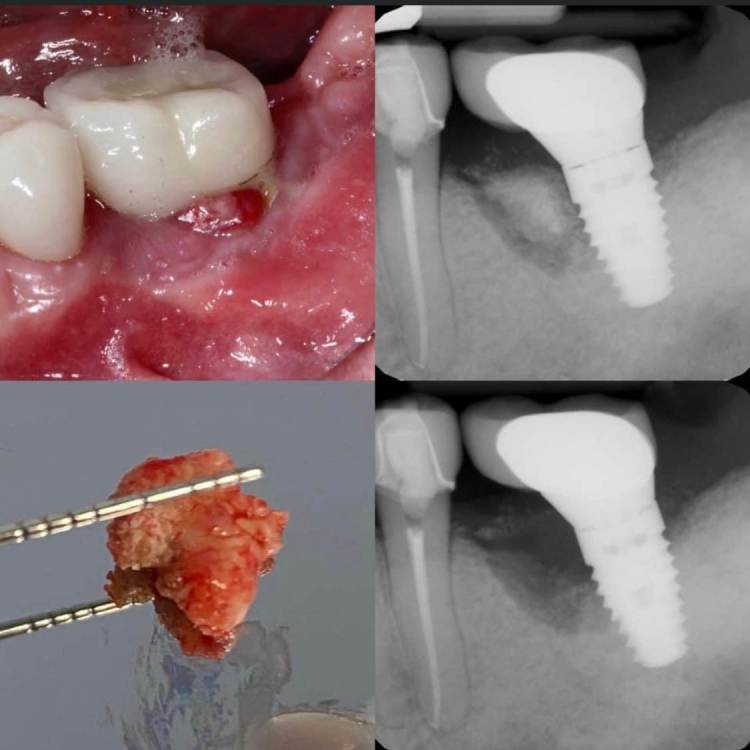

колесников Опубликовано 5 июля, 2022 Поделиться Опубликовано 5 июля, 2022 Здравствуйте коллеги. Год назад попалась публикация где описывался случай как ксеноаугментат секвестрировался спустя 12лет. Мне на днях попался аналогичный случай. Спустя 5 лет(графт bio-oss). Пусковым механизмом, вероятно ,был цемент ,попавший в придесневую шахту после фиксации. Ещё из интересного: интегрированный имплант (mis)удалён ключом на реверс. Вывод: чистый ксено-это не кость. 6 Ссылка на комментарий

колесников Опубликовано 6 июля, 2022 Автор Поделиться Опубликовано 6 июля, 2022 Дискомфорты только недавно появились. Консервация лунки не зло,нужно просто не сыпать чистый ксено. Используйте кортикальный алло и все будет отлично. 2 Ссылка на комментарий